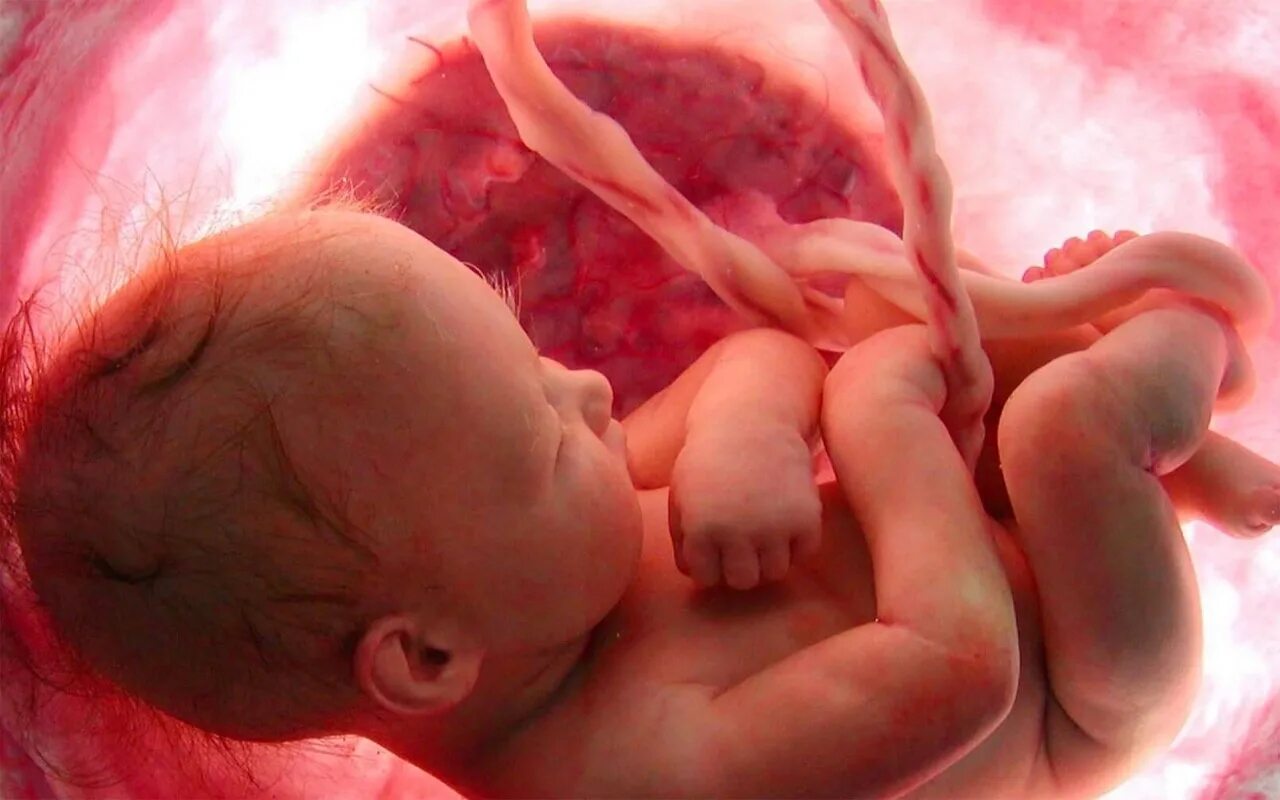

Ребенок в утробе 31 неделя